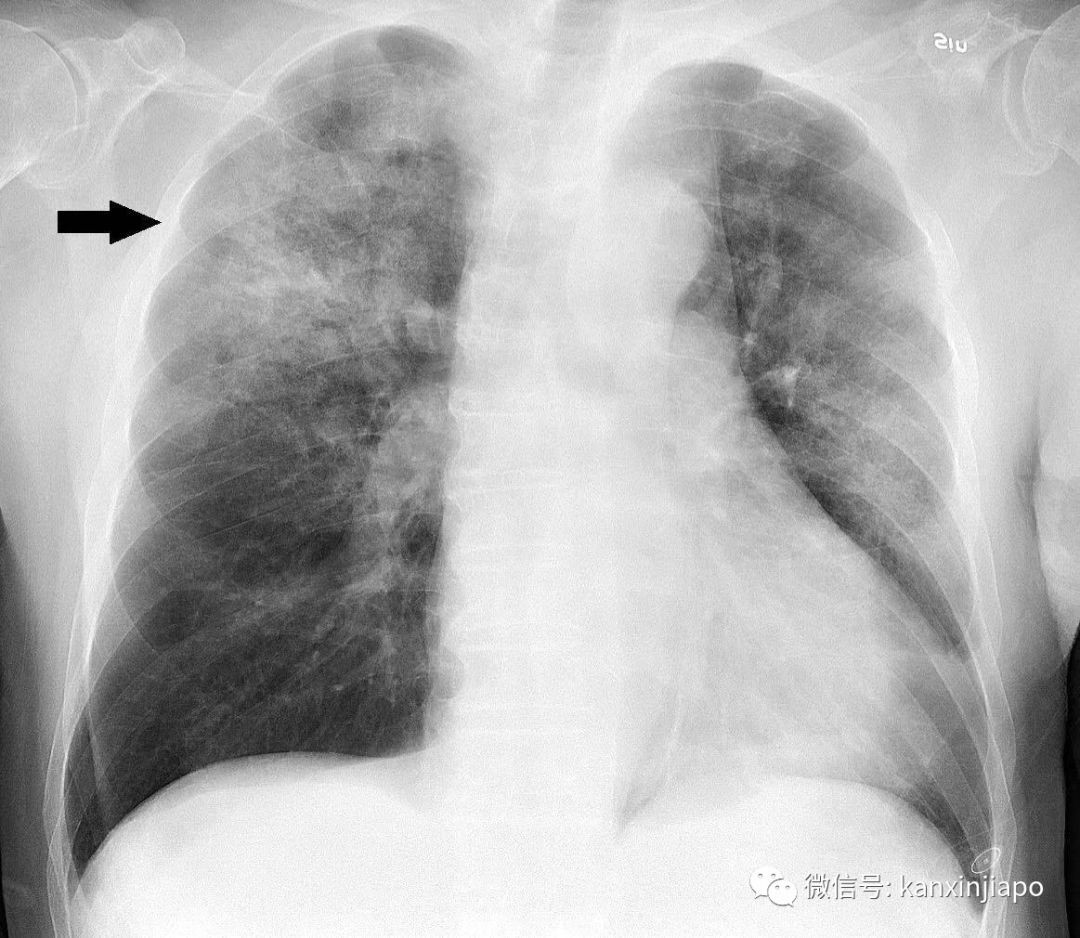

患者是一名近期去过武汉的3岁女童。出于安全考虑,女童被隔离并进行更仔细的观察治疗。经过一系列流行病学调查、临床评估及实验室结果显示,卫生部于今天证实这名女童对沙斯(SARS)、中东呼吸综合征(MERS-CoV)亦呈阴性反应。因此确认她得的只是在儿童呼吸道感染中常见的呼吸管道合胞病毒(respiratory syncytial virus)。

近日,中国湖北省武汉市爆出不明原因肺炎疫情,引发全球关注。

目前,中国武汉确证感染人数为44例,其中重症11例,其余患者生命体征总体稳定。